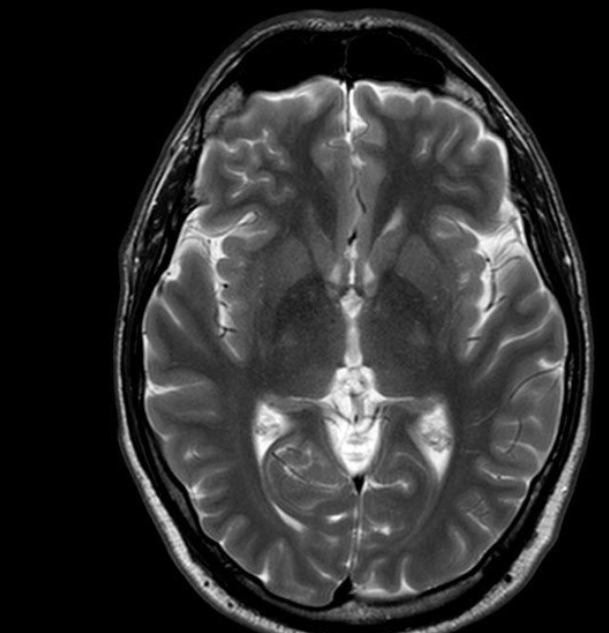

이 검사는 X선을 여러 각도에서 투사해 가슴 속을 단면으로 나누고, 컴퓨터가 이를 조합해 입체적으로 보여줍니다. 흉부ct로 볼수있는 질환 폐, 기관지, 심장, 혈관, 흉막, 림프절, 늑골까지 모두 관찰할 수 있어요. 몸을 절개하지 않고 내부를 볼 수 있으니 환자에게 부담이 적습니다. 조영제(혈관이나 염증 부위를 선명하게 보여주는 약물)를 사용하는 경우에는 정맥으로 주입하기도 하지만, 대부분은 통증이 거의 없습니다.

흉부ct로 볼수있는 질환 폐질환뿐 아니라 심장과 혈관, 흉막, 림프절, 뼈 구조까지 한 번에 보여줍니다. 폐렴, 결핵, 폐기종, 기관지확장증, 간질성 폐질환 같은 호흡기 질환은 기본이고, 폐에 생긴 작은 결절이나 혹도 세밀하게 확인할 수 있습니다. 폐암이나 전이암처럼 초기에 증상이 거의 없는 병은 CT로 발견되는 경우가 많아요.

흉부CT는 병이 있는지 없는지를 넘어서, 병의 진행 정도와 주변 장기 침범 여부까지 보여줍니다. 예를 들어 폐암의 경우, 5mm 미만의 아주 작은 결절까지 찾아내고, 종양이 혈관이나 기관지에 닿았는지도 확인합니다. 초기에 잡아내면 완치율이 크게 높아지죠.

또한 폐렴이 감염인지, 결핵성인지, 종양에 의한 것인지도 구분할 수 있습니다. 엑스레이에서는 그냥 ‘흐린 그림자’로만 보이던 것도, CT에서는 염증의 경계와 내부 구조까지 뚜렷하게 드러납니다.